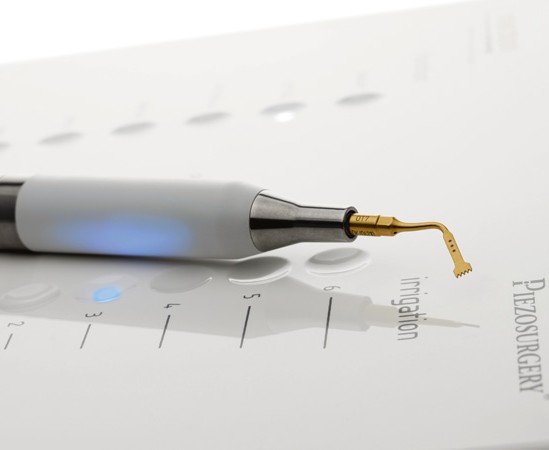

Implant Placement using surgical guides for precision, the titanium implant is placed into your jawbone, typically 30-60 minutes with local anaesthesia.